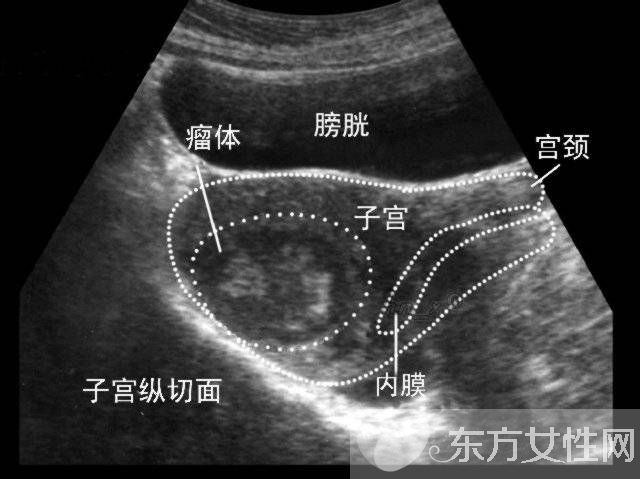

什么是子宮肌瘤?

子宮肌瘤是女性子宮內(nèi)多見的非惡性腫瘤,根據(jù)其在宮體內(nèi)肌肉分布位置的不同,可分為肌壁間肌瘤、漿膜下肌瘤和黏膜下肌瘤,不過,肌瘤也可以同時在多種位置生長。